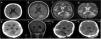

Los sarcomas granulocíticos son neoplasias sólidas compuestas de células mieloides inmaduras, de localización extramedular, asociadas a síndromes mieloproliferativos. La afectación del sistema nervioso central es muy infrecuente y puede desarrollarse tras un periodo de remisión completa, coexistir con o preceder a la enfermedad sistémica, siendo esta el elemento fundamental que orienta el diagnóstico radiológico y marca el pronóstico. En este trabajo, presentamos 2 casos de sarcoma granulocítico intracraneal, verificados desde el punto de vista patológico tras ser tratados mediante cirugía, y discutimos sus características clínicas, diagnósticas, terapéuticas y pronósticas tras realizar una revisión bibliográfica de la literatura científica destacada publicada hasta la fecha.

Granulocytic sarcomas are solid, extramedullary-located neoplasms composed of immature myeloid cells, associated with myeloproliferative syndromes. Central nervous system involvement is very rare and may develop either after complete remission, coexist with or precede the systemic disease, being the last one that guides the radiological diagnosis and marks the prognosis. In this work, we report 2 pathologically-verified cases of intracranial granulocytic sarcoma treated by surgical means. Their clinical, diagnostic, therapeutic and prognostic features are discussed in the light of the most relevant scientific literature published to date.